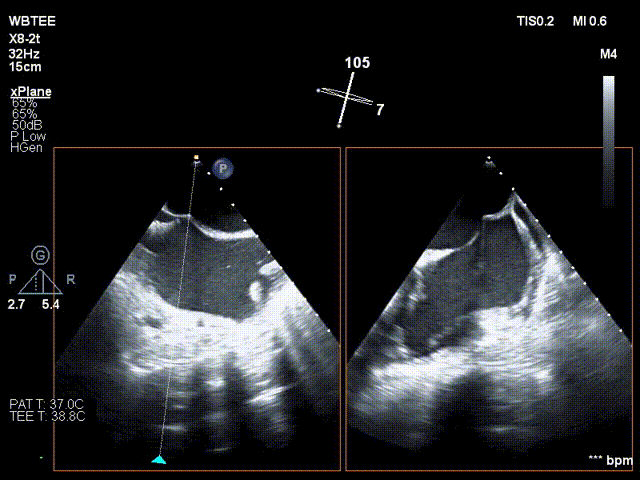

术前行经食道超声评估

原发性二尖瓣反流,反流程度4+;二尖瓣瓣口面积4.15cm²,平均跨瓣压差5mmHg,二尖瓣前叶(A2)长度23.35mm,二尖瓣后叶长度(P2)长度13.2mm;左室射血分数67%。患者手术风险高,操作难度大,经心脏瓣膜团队多次充分讨论评估后,决定行经导管二尖瓣缘对缘修复治疗。

术前MDT策略:从解剖结构来看二尖瓣后叶脱垂伴连枷涉及整个2区,累及3区和1区,宽度15mm左右,且连枷高度甩起高度有7-8mm,可见长达10.4mm的飘样回声,术前策略预计使用两个二尖瓣夹,较小的二尖瓣口面积和较高平均跨瓣压差,是一次高难度的挑战。